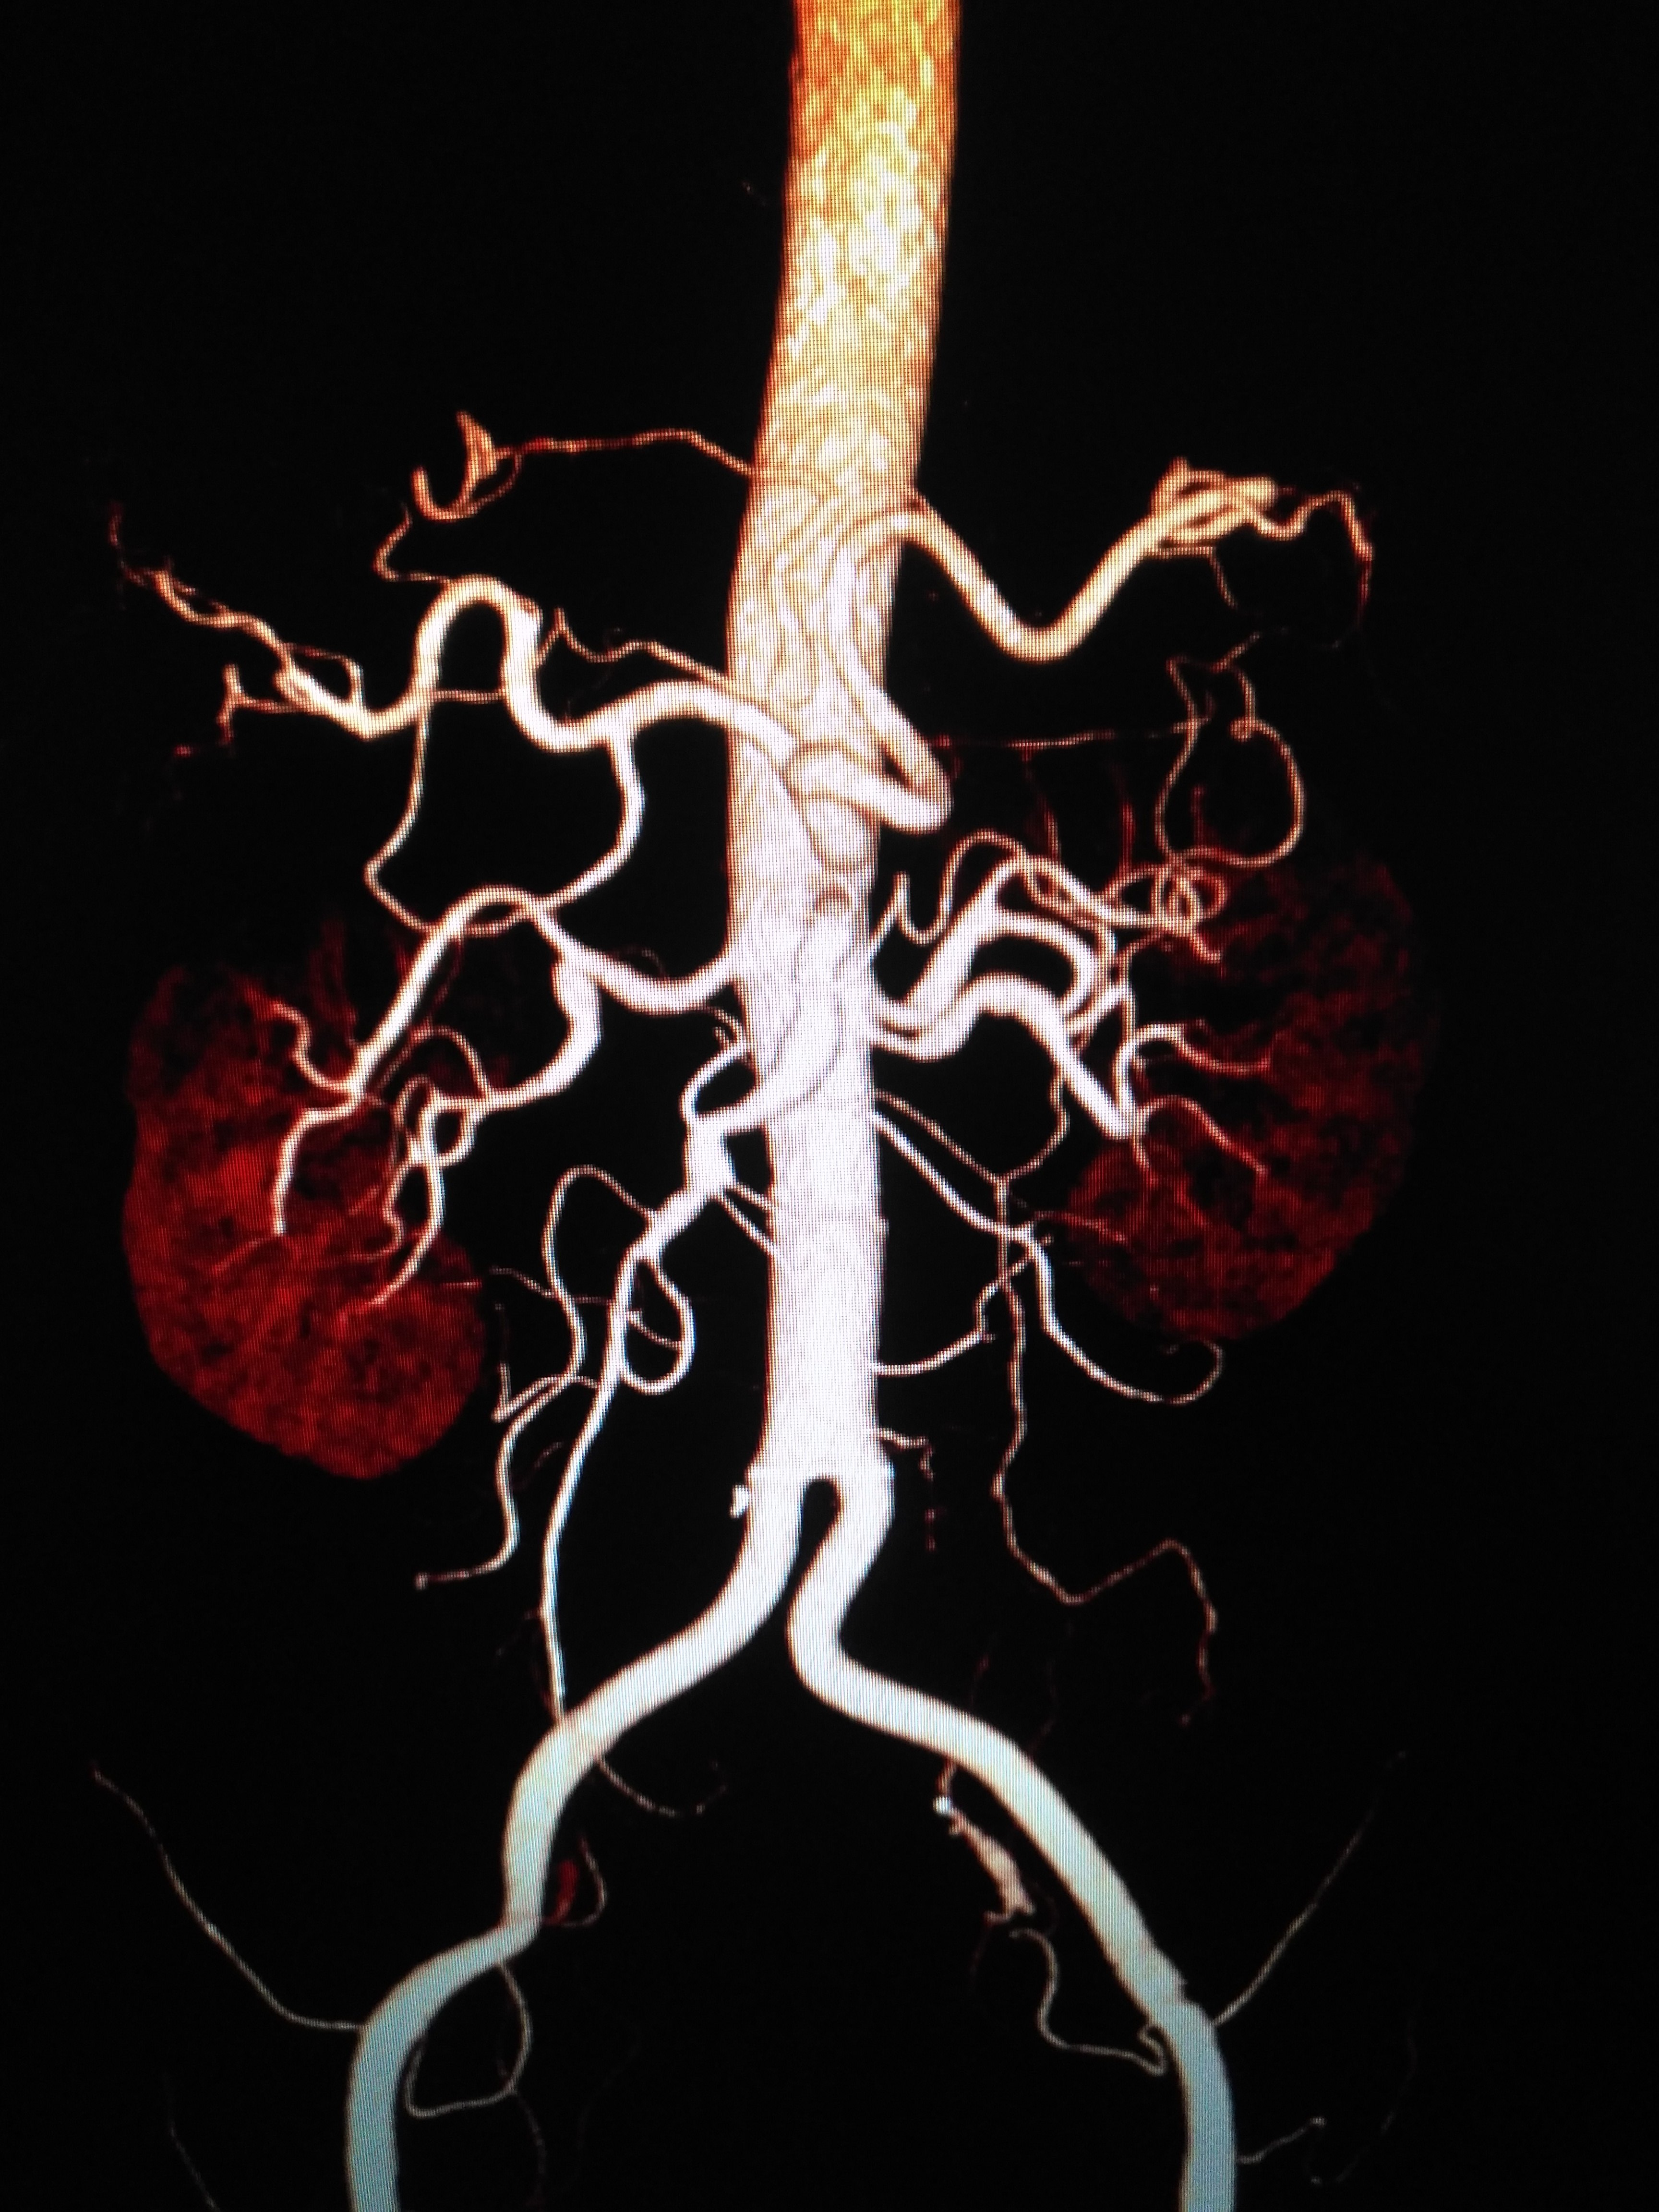

yinan li 的想法: 急诊腹主动脉瘤破裂,从鬼门关外面把人拉… - 知乎

图片尺寸1587x1080